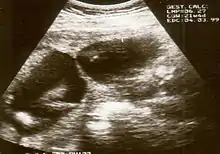

The diagnosis of constriction ring syndrome can be confirmed with an ultrasonography. The clinical manifestations can be extremely variable. It could be a single or multiple manifestation. This can be confirmed at the end of the first trimester or at the beginning of the second trimester.[13] But not every patient will be diagnosed at that moment, most will get this diagnosis at birth.

Individual strands are small and hard to see on ultrasound, so bands are detected indirectly because of the constrictions and swelling upon limbs or digits. Misdiagnosis is also common, so if there are any signs of amniotic bands, further detailed ultrasound tests should be done to assess the severity. 3D ultrasound and MRI can be used for more detailed and accurate diagnosis of bands and the resulting damage/danger to the fetus.